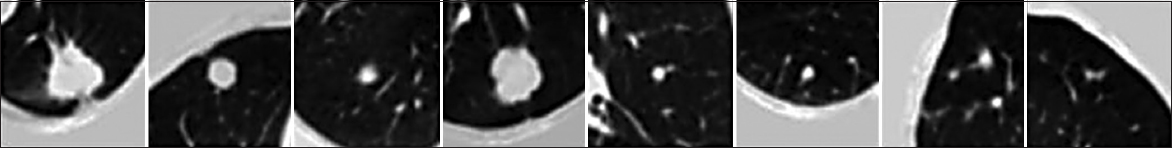

To improve the performance of preprocessing by adopting CLAHE to improve the input images contrast and certainly increases the accuracy and speed of nodule identification and reduce the computational load of network training and evaluation, therefore, to reduce the interference of unimportant lung regions processed on the evaluation outcomes, the obvious salient locations of each labeled image were cropped based on the node position provided in the annotation files, and the original image sizes were cropped to (96 × 96) pixels to retain the fully important private information as shown in Fig. 7.

thumblarge

Fig. 7. Pulmonary nodule segmentation results using U-Net convolutional neural network.